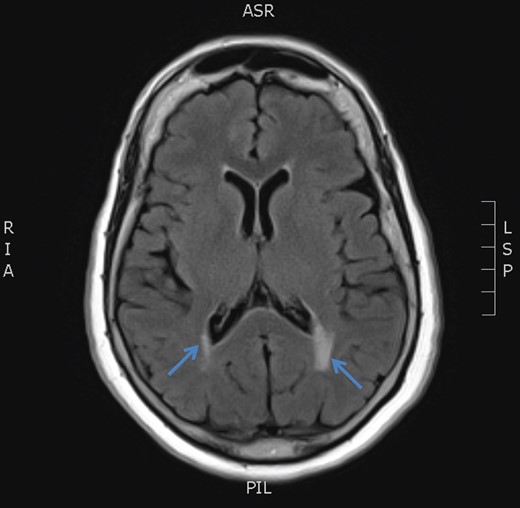

December 2015, she had a normal electroencephalogram (EEG). Subsequent MRI done January and March 2016 showed T2 Weighted Imaging Fluid Attenuated Inversion Recovery (T2WI/FLAIR) changes in the right medial temporal lobe (Fig. 2). Right hippocampal signal change was suspicious of low-grade glioma with a differential diagnosis of post viral limbic encephalitis. There was no enhancement with intravenous gadolinium administration and no other suggestion of a focal malignant disease. She remained clinically well and repeat MRI done October 2016 showed areas of signal abnormalities focused around the posterior horns of the lateral ventricles and but no sign of right temporal lobe low-grade glioma or encephalitis (Fig. 3). All of these signal changes resolved completely with repeated MRI and she had no further seizures.

MRI brain axial T2 FLAIR sequence (October 2016) depicting resolution of right medial temporal lobe high signal but prominence of periventricular hyperintensity in periventricular white matter (arrows).